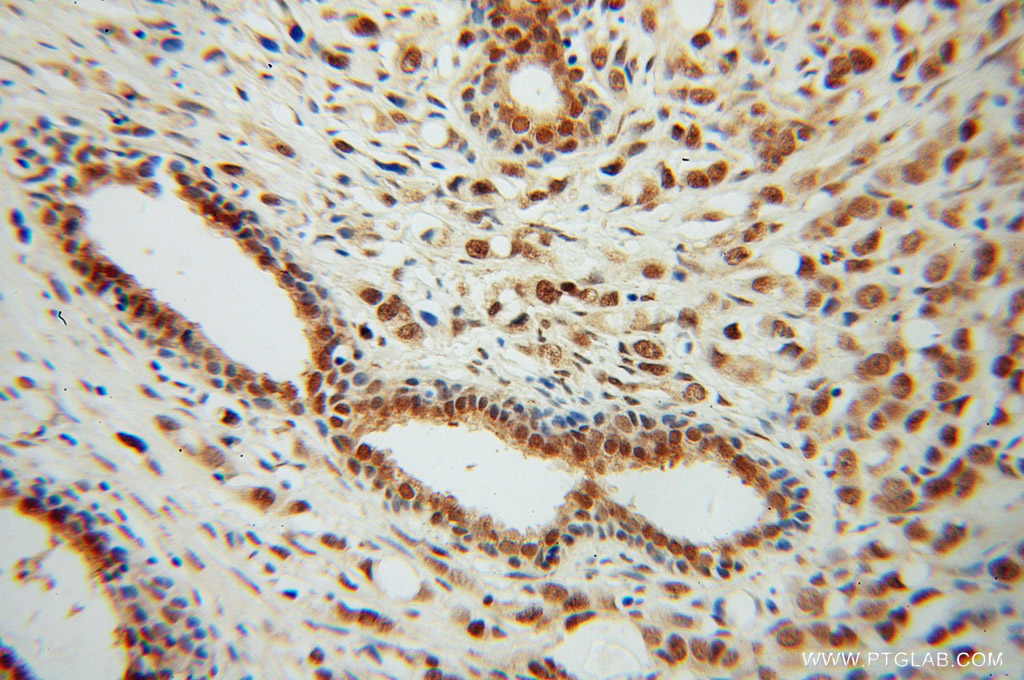

| Positive IHC detected in | human prostate cancer tissue Note: suggested antigen retrieval with TE buffer pH 9.0; (*) Alternatively, antigen retrieval may be performed with citrate buffer pH 6.0 |

| Immunohistochemistry (IHC) | IHC : 1:20-1:200 |